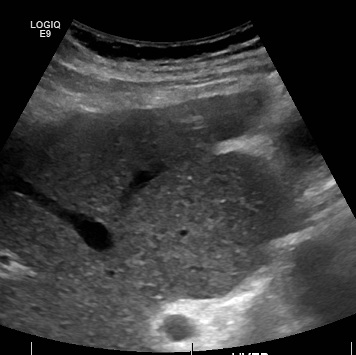

Compared to primary liver tumors, liver metastasis is more common.

Clinical diagnosis of liver metastasis may reveal a nodular free edge of the liver and hepatomegaly.

Radiology of liver metastasis usually show numerous nodules in the liver.